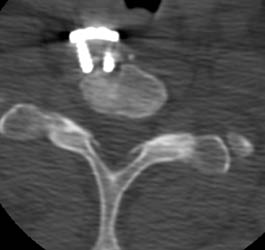

Scout image from a CT obtained 3 months later suggests ventral displacement of the

bone graft and fixation plate. |

This axial CT taken at the same time shows to

better advantage how the distal screws are fully out of the ventral cortex of C7

on the right hand distal screw and only 1 thread of the left hand distal screw

remains in the bone itself. The fixation plate is also 1cm ventral to the body

of C7 at this level.